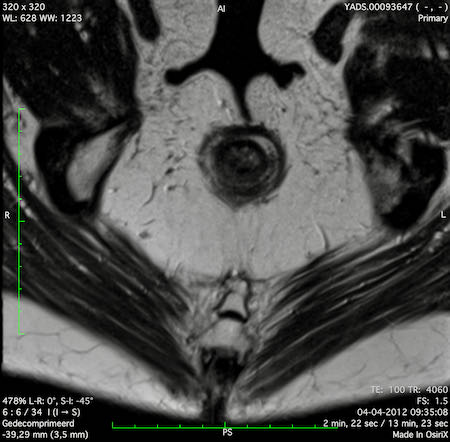

Hình ảnh

Các hình ảnh được cung cấp cho thấy ung thư biểu mô tế bào nhẫn với tình trạng dày lan tỏa thành trực tràng, hình ảnh bia bắn điển hình, và sự xâm lấn mỡ mạc treo trực tràng.